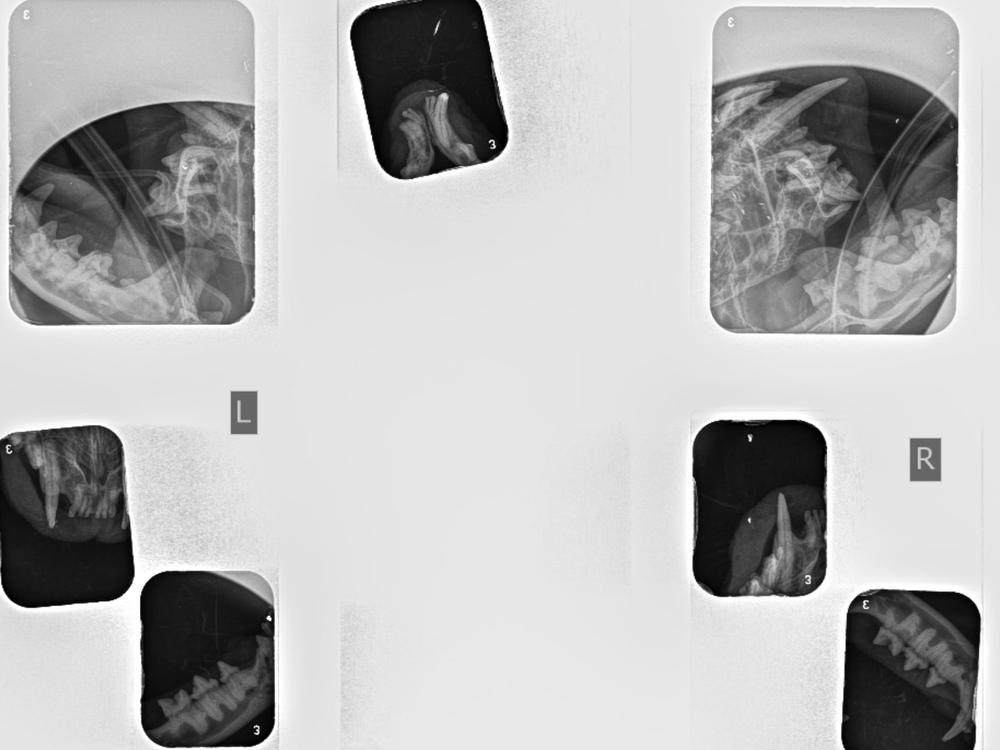

Recently, Liana needed a dental procedure at the vet. During the visit, X-rays revealed something we weren't expecting - she had a fractured lower jaw! A special wire was placed to help her jaw heal, but unfortunately, it hasn't healed properly and is still unstable.